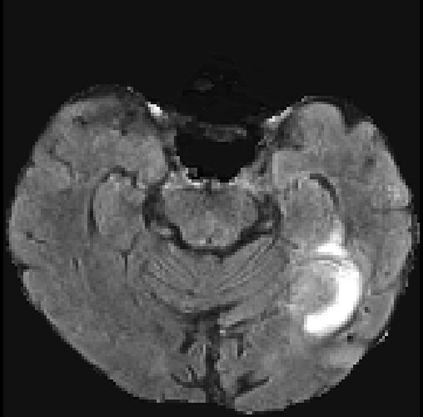

Despite the state-of-the-art performance for medical image segmentation, deep convolutional neural networks (CNNs) have rarely provided uncertainty estimations regarding their segmentation outputs, e.g., model (epistemic) and image-based (aleatoric) uncertainties. In this work, we analyze these different types of uncertainties for CNN-based 2D and 3D medical image segmentation tasks. We additionally propose a test-time augmentation-based aleatoric uncertainty to analyze the effect of different transformations of the input image on the segmentation output. Test-time augmentation has been previously used to improve segmentation accuracy, yet not been formulated in a consistent mathematical framework. Hence, we also propose a theoretical formulation of test-time augmentation, where a distribution of the prediction is estimated by Monte Carlo simulation with prior distributions of parameters in an image acquisition model that involves image transformations and noise. We compare and combine our proposed aleatoric uncertainty with model uncertainty. Experiments with segmentation of fetal brains and brain tumors from 2D and 3D Magnetic Resonance Images (MRI) showed that 1) the test-time augmentation-based aleatoric uncertainty provides a better uncertainty estimation than calculating the test-time dropout-based model uncertainty alone and helps to reduce overconfident incorrect predictions, and 2) our test-time augmentation outperforms a single-prediction baseline and dropout-based multiple predictions.